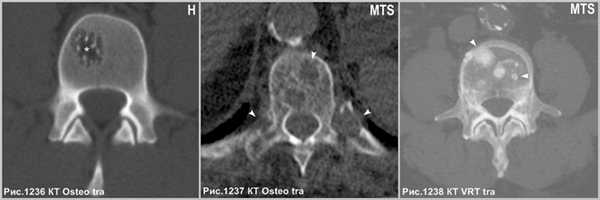

Эти опухоли растут медленно и, в большинстве случаев, бессимптомны, если они не оказывают влияния на окружающие структуры. Иногда они могут проявиться в виде отека, ощутимой или заметной массы, особенно в черепе. Могут осложняться патологическим переломом. Изредка они могут вызвать компрессию спинного мозга или его корешков из-за распространения опухоли в кость или мягкие ткани. Наличие жира коррелирует с отсутствием прогрессирования опухолевого роста. Напротив, опухоли, содержащие мало жира или опухоли без жира, вероятнее, будут эволюционировать и расти [87]. Для лечения применяется: лучевая терапия, эмболизация для уменьшения операционной кровопотери и хирургическая резекция, особенно если болезнь осложняется компрессией спинного мозга с последующей вертебропластикой. Так же используется внутриочаговая инъекция этанола и цементирование полости во избежание внезапных травматических осложнений.

![heangioma_9]()

Итраоперационный рентгеновский контроль, посредством электронного оптического преобразователя, демонстрирует компактный участок плотного медицинского цемента, выполняющего полость крупной гемангиомы (головки стрелок на рис.1239.а), после вертебропластики, призванный стабилизировать тело пораженного позвонка и предотвратить вероятность патологического перелома. Следы вертебропластики в виде участка остеосклероза на МРТ (головки стрелок на рис.1239.б) и на КТ (головки стрелок на рис.1239.в). Визуализируется канал от прохождения иглы в левой дужке позвонка (стрелка на рис.1239.в).